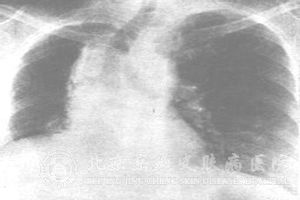

放射性肺炎是在一些胸部恶性肿瘤的患者接受放疗的过程中很容易发生的肺部炎症反应,对于其具体的发生机制及其原因,我们了解还不是很多,下面就来看看专业的解释。

放射性肺炎的发生及其症状严重程度于多种因素密切相关,如放射的方法、放射剂量、放射范围以及放射速度。

如果患者在6周内接受小于2000rad的剂量则发生肺炎的可能较小;当超过4000rad时肺炎的发生率就会明显增高,当放射剂量超过6000rad时,就会导致放射性肺炎。

另外,随着放射范围的不断扩大,也会导致发生率的提高;范围较大的照射比局部的照射所产生的损伤也更为严重。

随着照射速度的加快,也会越来越容易导致肺组织出现损伤。

除此之外,个人对于放射线的耐受性低、肺部本身患有肺炎、气管炎、慢性支气管炎、慢性阻塞性肺部疾病或者再次放疗等因素均可对放射性肺炎的发生起到增加作用,一般老人或者儿童对放疗的耐受都较差,还有些化疗药物还可加重肺部的放疗反应。